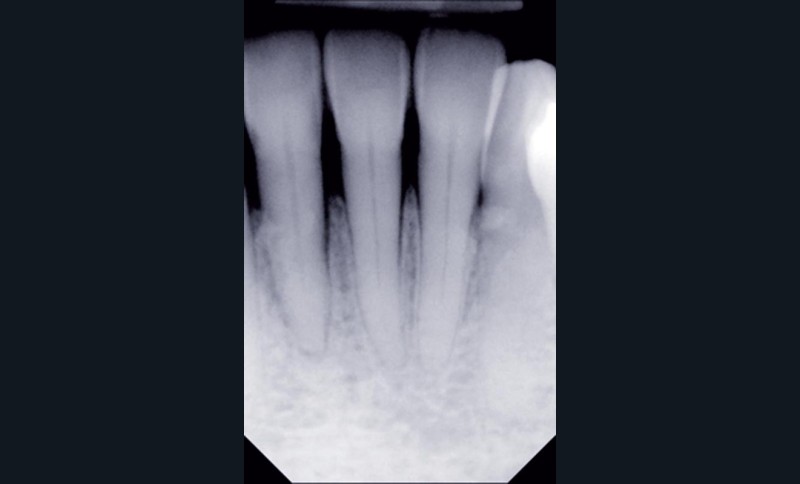

Au-delà du préjudice esthétique, il induit des forces importantes en direction vestibulaire sur les incisives mandibulaires. Ces incisives présentent une légère mobilité. La radio rétro-alvéolaire montre un élargissement desmodontal et une perte osseuse verticale sans cratérisation ni inflammation (fig. 3).